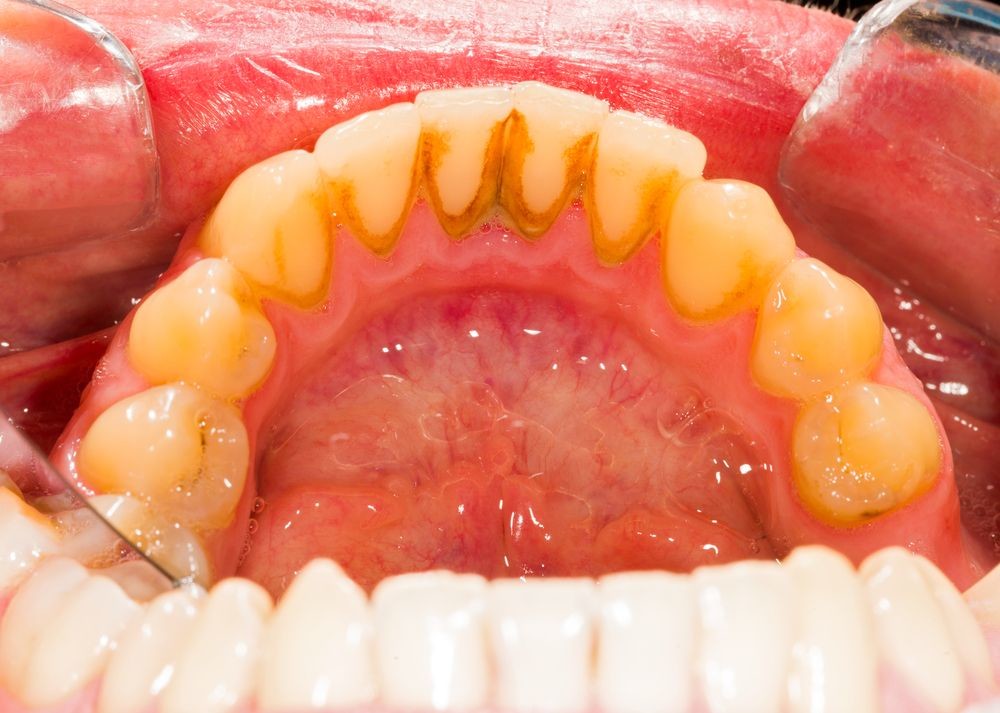

Oral biofilms, a concern for all dental professionals

Biofilms are a collective of one or more types of microorganisms that can grow on many different surfaces. Microorganisms that form biofilms include bacteria, fungi and protists.

One common example of a biofilm dental plaque, a slimy buildup of bacteria that forms on the surfaces of teeth. Pond scum is another example. Biofilms have been found growing on minerals and metals. They have been found underwater, underground and above the ground. They can grow on plant tissues and animal tissues, and on implanted medical devices such as catheters and pacemakers.

Role of oral biofilm in the aetiology of disease:

Oral biofilm is medically important because it has broad implications for maintaining not only oral health but also systemic health. It is estimated that biofilms account for over 80% of microbial infections in the body. Research has undoubtedly shown that biofilm-dependent infections, including oral diseases such as caries, and periodontal and endodontic disease, thus pose major public health and cost concerns globally.

Periodontal disease, in particular, is considered one of the most prevalent diseases worldwide, affecting up to 50% of the world’s adult population, according to FDI World Dental Federation. Previous research has established connections between periodontal disease and preterm births, low birthweight, diabetes, and risk factors associated with cardiovascular disease and stroke. Globally, periodontitis is responsible for an estimated US$54 billion per year in lost productivity and a major portion of the US$442 billion spent annually on oral disease, according to the European Federation of Periodontology.

Control of oral biofilm:

Owing to the vast implications of oral biofilm for dental and general health, its effective control represents a major challenge. There is no question that the formation and maturation of oral biofilm need to be tackled by dental professionals across all specialties in all countries worldwide.